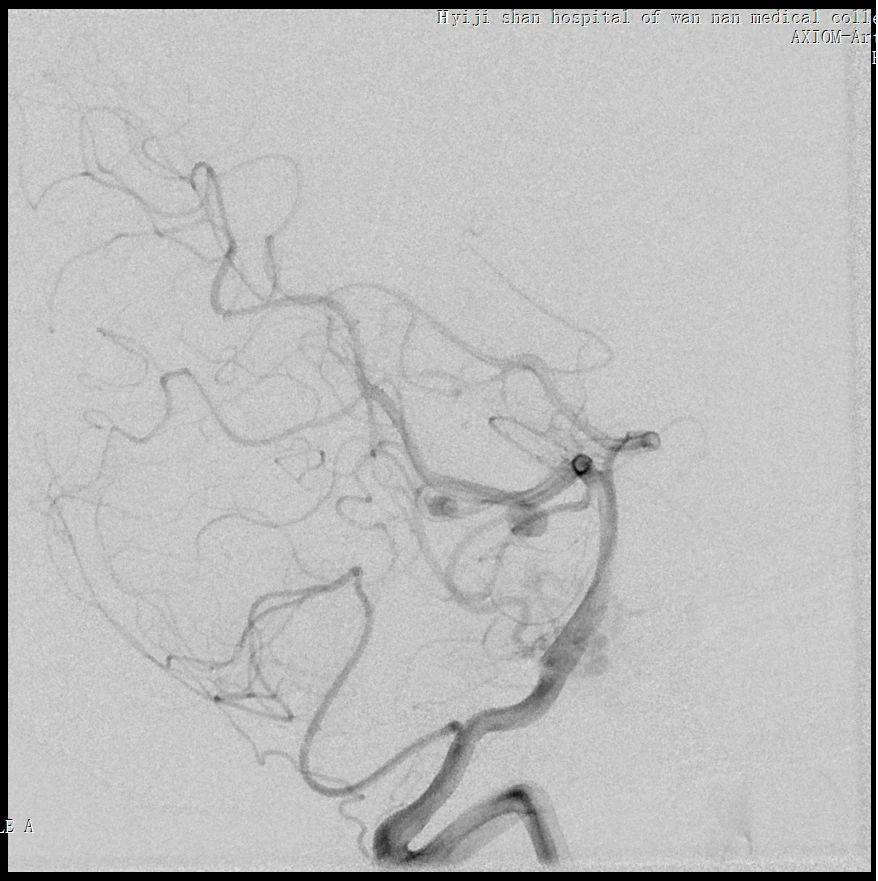

将Echelon 10微导管超选至右侧大脑中动脉分叉部分支血管远端,微导管造影确认系畸形团供血动脉,DMSO冲管后注射Onyx胶再行造影,可见该分支血管远端闭塞,予以撤出Echelon 10微导管。

用Apollo微导管超选大脑中动脉M1段分支血管直至畸形团内,进行微导管造影确认微导管进入畸形团,DMSO冲管,缓慢注射Onyx 18,路图下可见胶在畸形团内弥散,最后颈内动脉造影可见畸形团完全不显影,但是胶反流导致拔管困难,透视下可见血管移位变形明显。